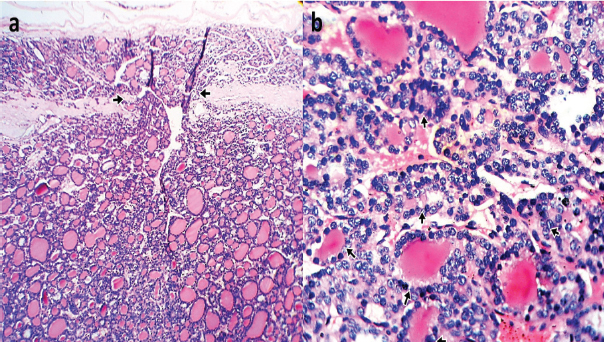

Sixty-one (61) cases of TCs were identified in this study constituting 10.8% (61/564) of thyroidectomy specimens received at our hospital’s Morbid Anatomy Department during the 15 year period under review. There were 51 (83.6%) females and 10 (16.4%) males giving a ratio of 5.1:1, and a mean age of 45.9 years [Table/Fig-1]. The most common histologic type was papillary thyroid carcinoma 26 (42.6%) cases [Table/Fig-2], followed by follicular carcinoma 23 (37.7%) cases [Table/Fig-3], medullary thyroid carcinoma 3 (4.9%) cases [Table/Fig-4a], anaplastic carcinomas 2 (3.3%) cases [Table/Fig-4b], Non-Hodgkin lymphoma 1 (1.6%) case and metastatic squamous cell carcinoma 2 (3.3%) cases. Three (4.9%) cases of mixed follicular/papillary carcinoma and one (1.6%) case of mixed papillary/anaplastic carcinoma were also identified in this study.

Photomicrograph of Papillary carcinoma showing: (a) Conventional type with complex branching and randomly oriented malignant papillary structures lined by optically clear [Orphan Annie] nuclei [short arrows] (H & E Stain X400); (b) Follicular type with proliferating atypical follicles lined by optically clear [Orphan Annie] nuclei, [short arrows] (H & E Stain X400).

Photomicrograph of Follicular carcinoma of thyroid showing: (a) Capsular transgression [short arrows] by the malignant follicular proliferation (H & E Stain X100); (b) Proliferation of atypical follicles lined by hyperchromatic cells [short arrows] (H & E Stain X400).